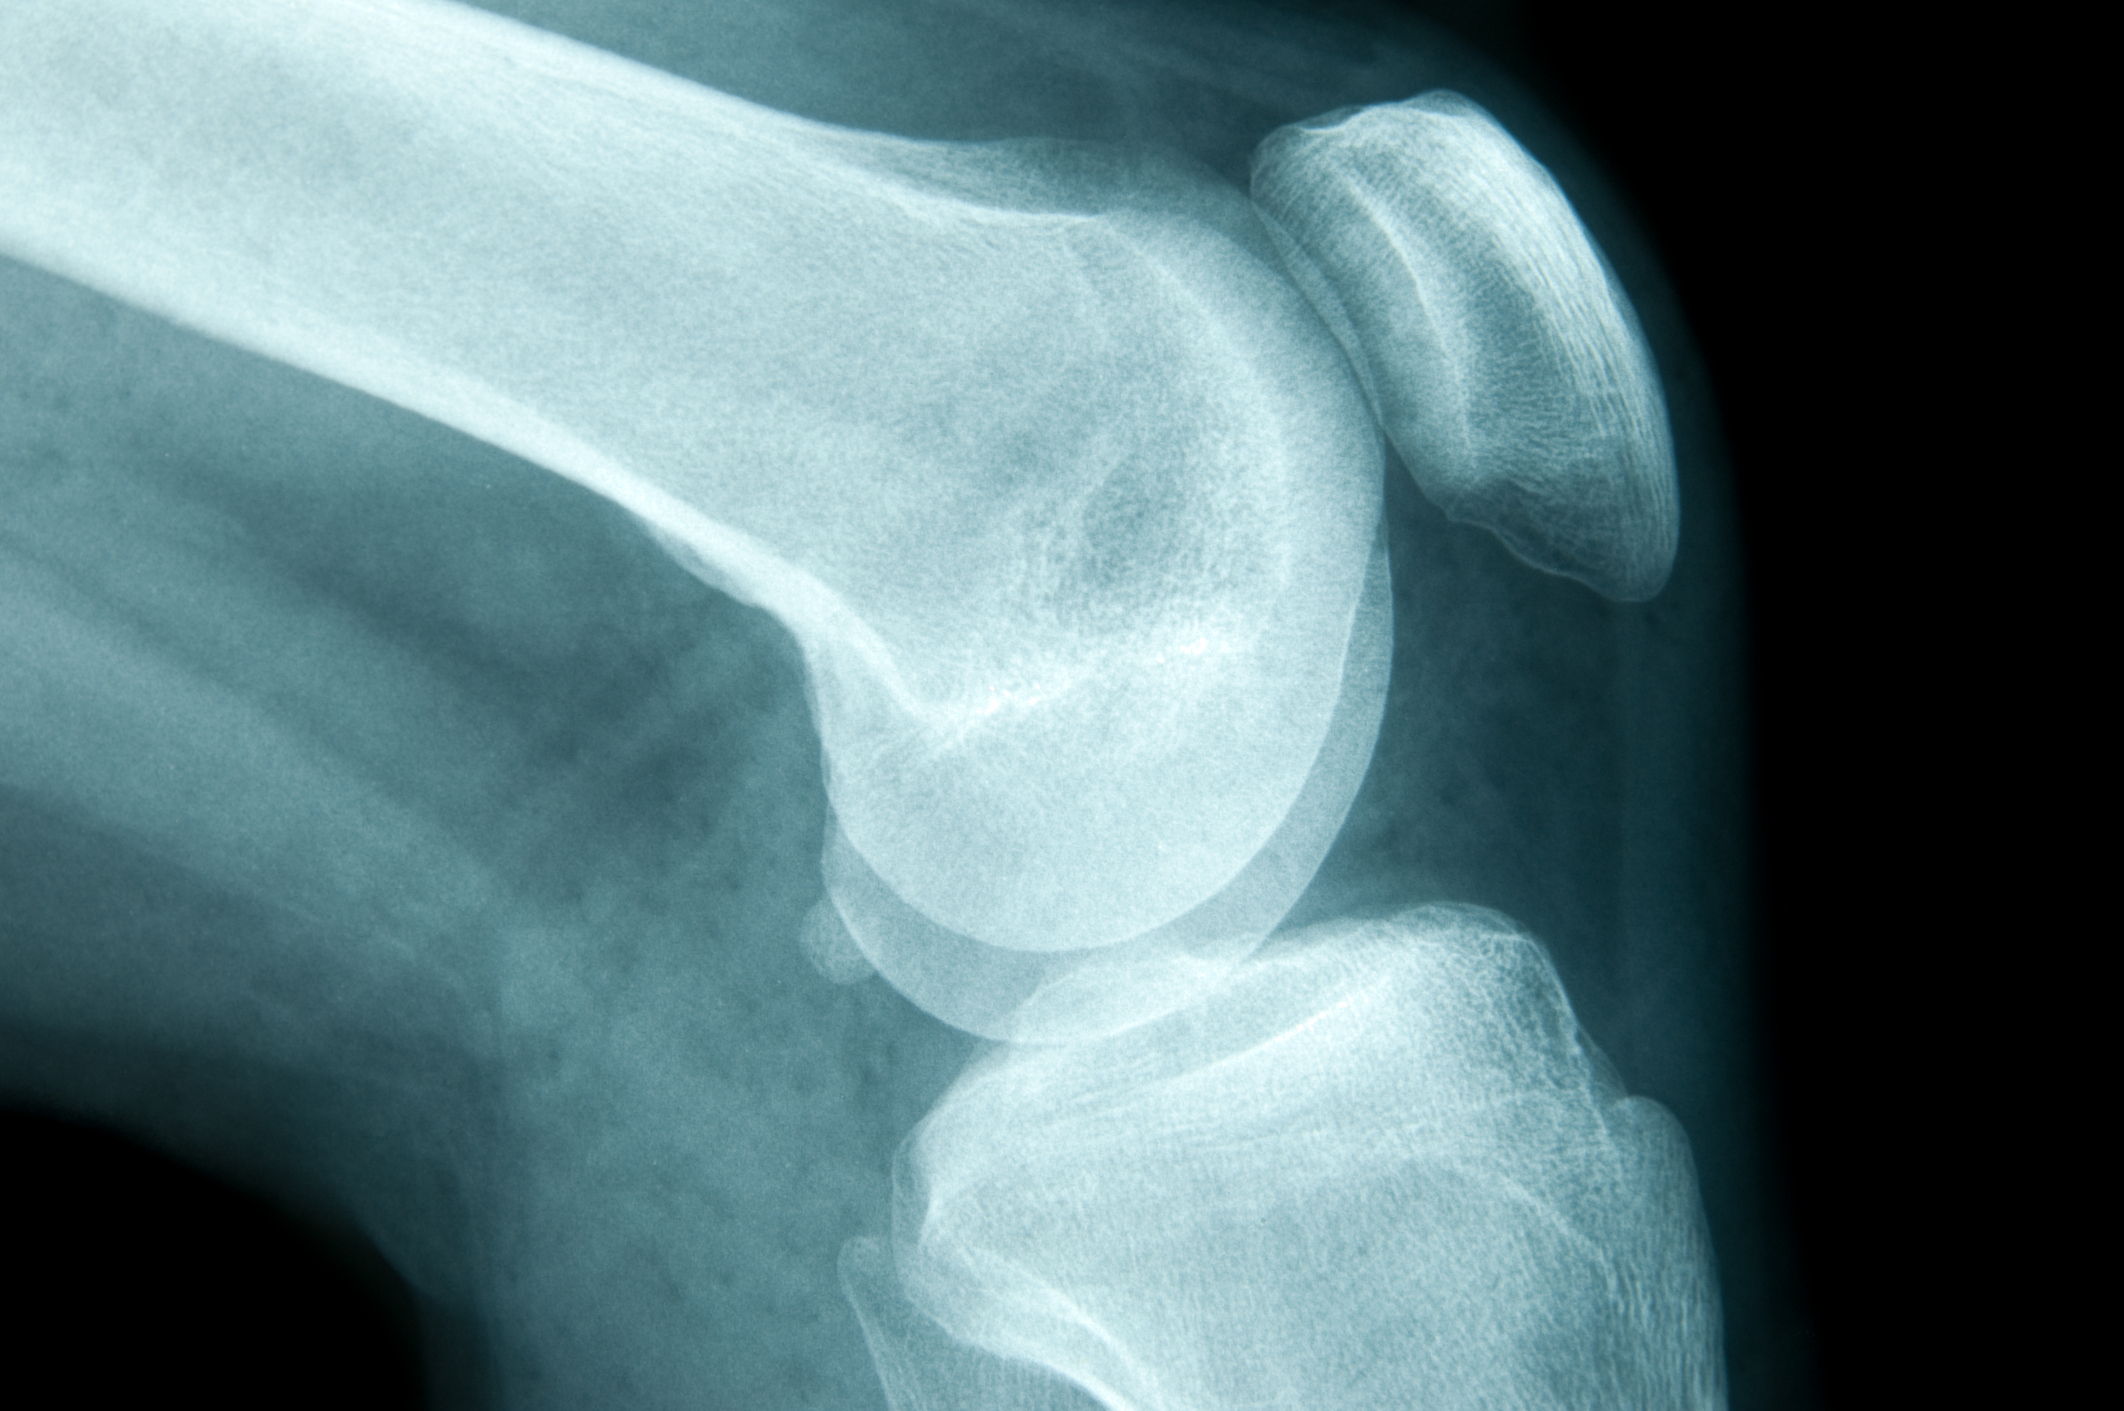

It’s estimated that many of the 1.3 million Australians suffering from osteoporosis don’t realise they have the “silent disease” until they break a bone, health experts say.1,2

But there are also a few myths around osteoporosis, including that it only affects menopausal women.3

Speaking on The Big O Show with Dr Sally Cockburn, Professor Ebeling explained it’s a disease that affects both men and women alike.3

“It’s not a painful condition like osteo-arthritis.

“We don’t know we’ve got it unless you fall over and break something.”2